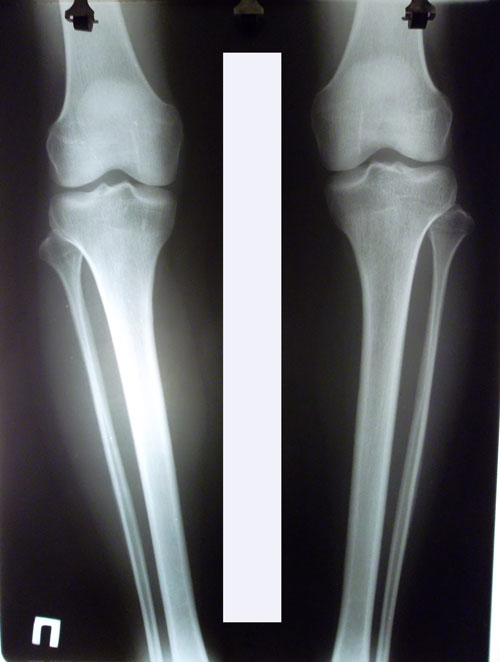

У пациентки плоскостопие 2-ой степени.

26 лет.

Дата операции 08.10.2015г.